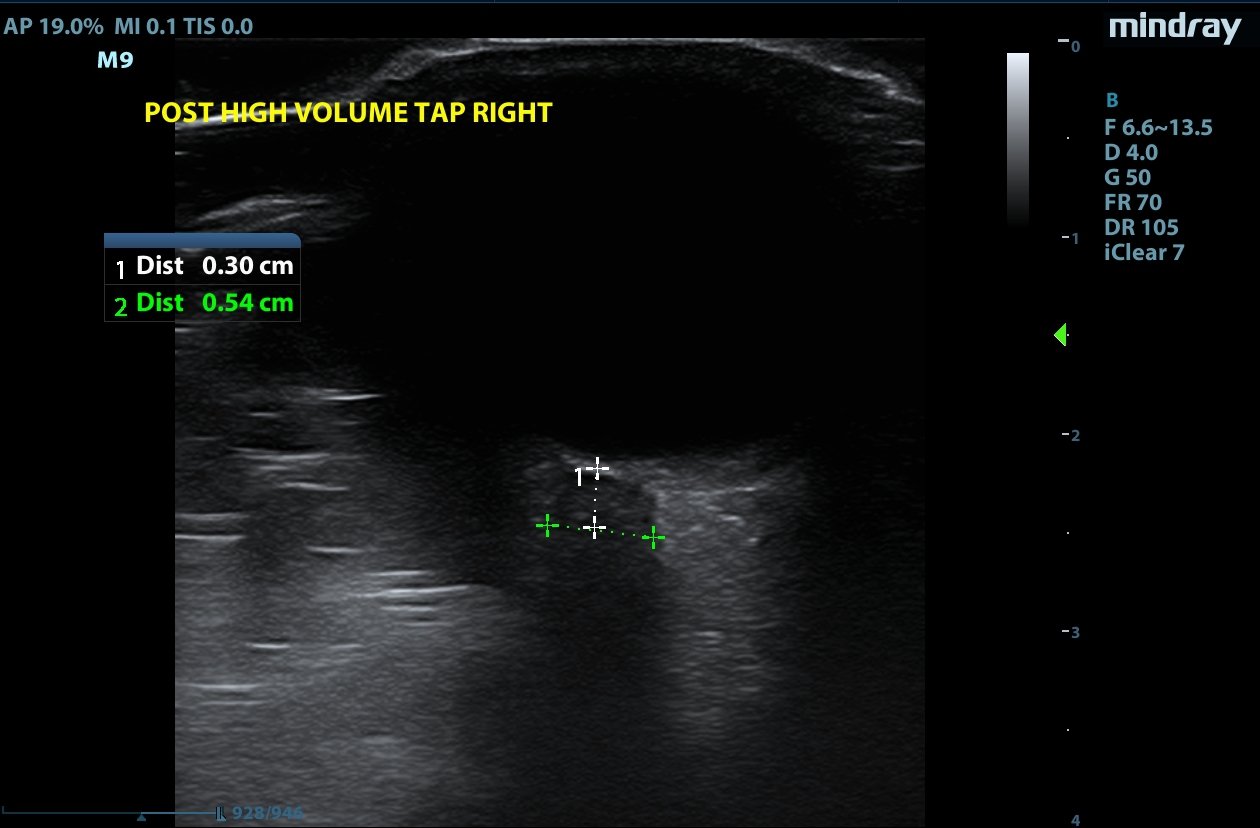

Optic nerve sheath diameter (ONSD) was measured via ultrasound with diameter 5.7mm on left and 6.2mm on right. In order to measure ONSD via optic ultrasound the high-frequency linear array probe (7.5-10-MHz or higher) is utilized in B-mode. The patient is positioned supine and an occlusive dressing, such as Tegaderm, is placed over a closed eyelid with copious conductive gel on top of the dressing. Being careful not to put pressure on the globe, an axial cross-sectional image of the globe is obtained. As demonstrated in the image “annotated left eye ONSD pre-lumbar puncture,” there are two main anechoic areas of the globe, the anterior chamber and the vitreous humor. These anechoic structures are separated by the hyperechoic iris, which surfaces the hyper-echoic-lined lens. At the back of the vitreous humor is the retina, which leads posteriorly into the optic nerve. The optic nerve is the hypoechoic structure posterior to the retina and surrounded by the hyperechoic subarachnoid space, which is encased by the hypoechoic dura mater. The outer edge of the hypoechoic dura matter is where the ONSD is measured.1 The user applies calipers to measure 3mm perpendicularly behind the retina along the hypoechoic optic nerve, and at this level the transverse dimensions of the ONSD are measured using calipers as shown in the images.

Computed tomography (CT) of the head was performed and showed no abnormalities. Lumbar puncture was performed in left lateral decubitus position revealing elevated opening pressure of 29cm H2O. Thirty-five mL of clear cerebral spinal fluid was drained and was negative for all infectious studies.  Optic nerve sheath diameter was again measured post-lumbar puncture with diameters 5.4mm on left and 5.4mm on right.